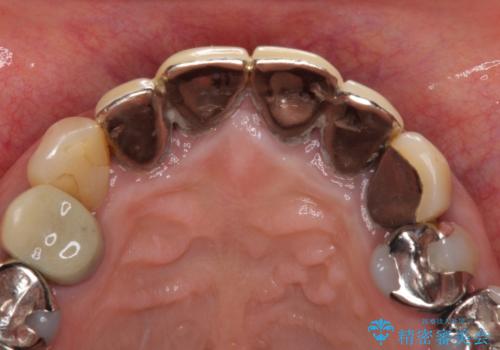

- 保険診療で装着した前歯のクラウンの変色を気にして来院された患者様です。

保険診療では樹脂を用いた素材で製作するため、水分が吸収されやすく、一緒に色素が取り込まれるために変色をしてしまいます。

また、裏打ちに主に銀を用いた金属材料を使用するため、金属自体が黒くなったり、イオンとなり溶け出したりして、歯肉ラインが黒くなってしまうことがあります。

金属の土台を歯の色に近いものへと変更した上で、オールセラミッククラウンにて補綴することとしました。